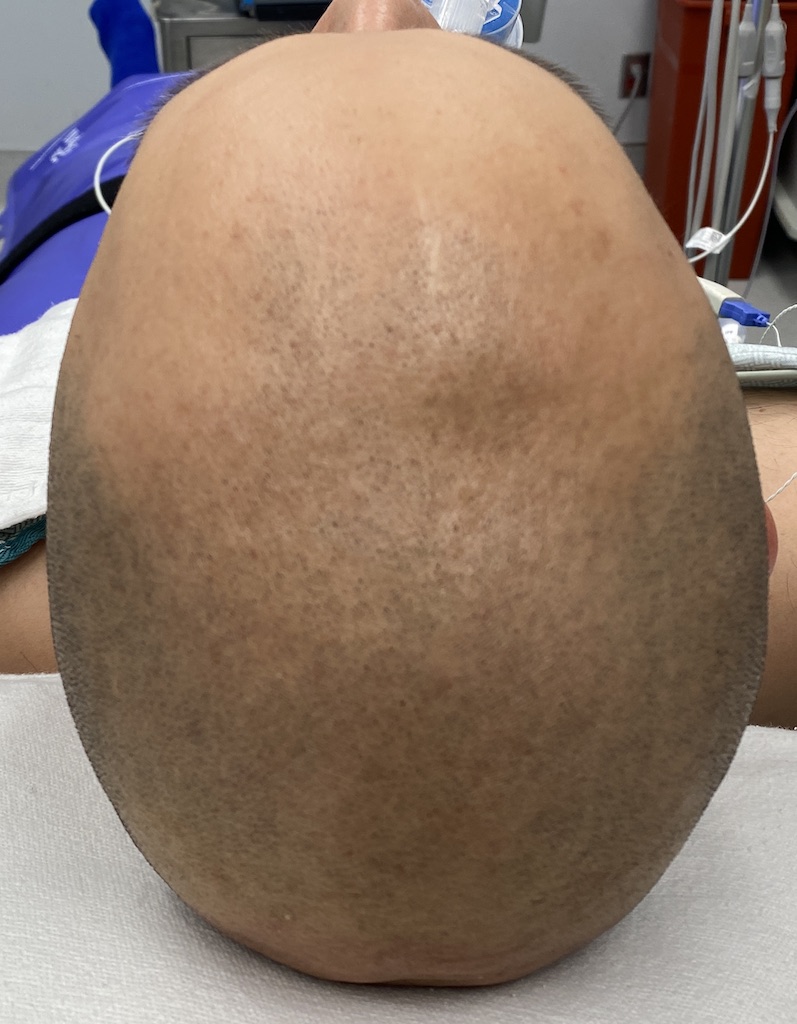

Desire for reduction of prominent occipital knob deformity.

Intraoperative result from occipital knob skull reduction through a direct small scalp incision.

Desire for reduction of prominent occipital knob deformity.

Intraoperative result from occipital knob skull reduction through a direct small scalp incision.